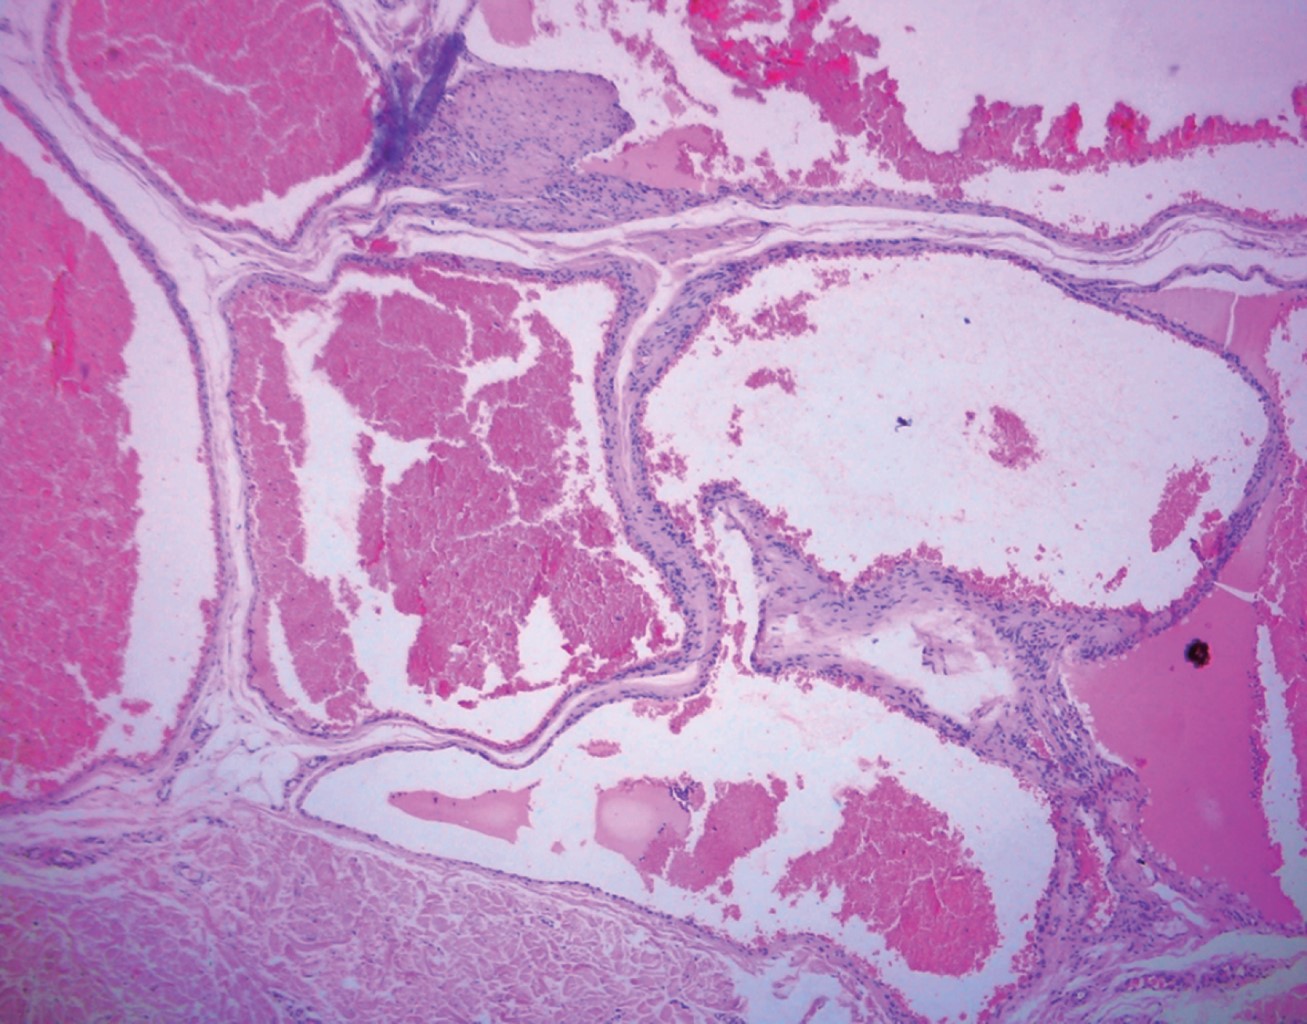

Se hizo biopsia escisional de ambas lesiones; las imágenes del estudio histopatológico se muestran en las Figuras 5 y 6.

El diagnóstico se basa en las características de topografía, morfología y sintomatología acompañante, y se confirma mediante la realización de una biopsia. En la histopatología se observan células glómicas, vasos sanguíneos y músculo liso; según el componente que predomine pueden categorizarse como TG sólido (pocas estructuras vasculares y células musculares escasas), glomangioma (con componente vascular prominente) o glomangiomioma (con predominio del componente vascular y de células musculares lisas). Los TG sólidos son el subtipo más frecuente (73%), seguidos de los glomangiomas (25%). Los TG se tiñen positivo para la actina (marcador de músculo liso).2,4,10

Figura 5

Figura 6